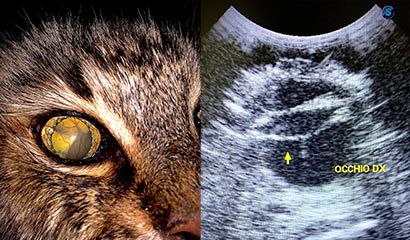

È una patologia dell’occhio comune nel gatto anziano in cui si realizza un più o meno completo distacco della retina dal fondo dell’occhio (fig.1).  La retina è costituita da numerosi strati in cui troviamo i fotorecettori (bastoncelli e coni) grazie ai quali si rende possibile la visione. Alla visita clinica il gatto presenterà improvvisa “cecità” con pupille molto dilatate (midriasi) e una ridotta risposta a uno stimolo luminoso.

Oltre alla visita oculistica del fondo dell’occhio, altra utile tecnica per la diagnosi è l’esame ecografico dell’occhio